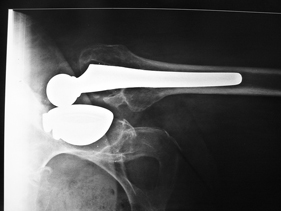

rivision total hip replacement for dislocation and severe bone defect

anterior-posterior view of left hip

lateral view of left hip